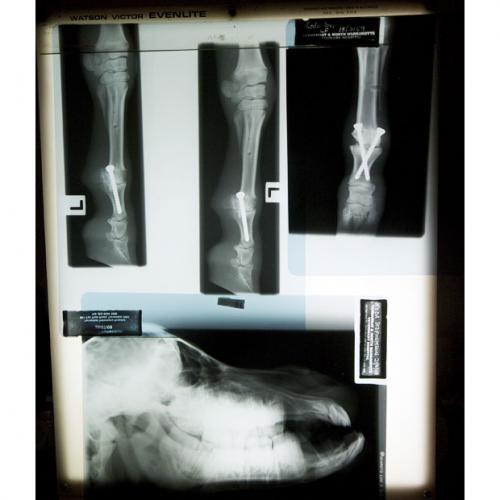

Хотя попал он к доктору как раз из–за проблем со здоровьем – Линчу пришлось прооперировать ноги Кода…

Самая маленькая лошадь живёт в Австралии

А сейчас ветеринар готовиться удалить несколько взрослых зубов карликового коня, которые не вмещаются в его миниатюрную челюсть…